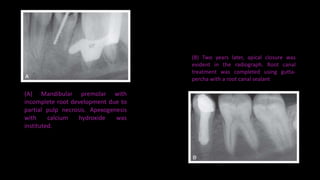

(A) Mandibular premolar with

incomplete root development due to

partial pulp necrosis. Apexogenesis

with calcium hydroxide was

instituted.

(B) Two years later, apical closure was

evident in the radiograph. Root canal

treatment was completed using gutta-

percha with a root canal sealant